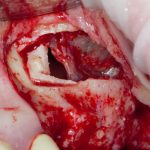

Подготовка костного ложа и фиксация аутотрансплантата

Возвращаемся к основной операционной области. Еще раз посмотрим на альвеолярный гребень, поофигеваем от его ширины и моих грандиозных планов:

Я зафиксировал костный блок практически без адаптации на несколько винтов. Обрати внимание, что винты находятся в зоне, где не планируется установка имплантатов. Фиксация должна быть надежной, поскольку мне еще предстояла подготовка лунок для имплантатов. Трех винтов для этого вполне достаточно.

Дальнейшая адаптация костного блока свелась к сглаживанию острых краев. После чего я приступил к подготовке лунок и установке имплантатов.

Установка имплантатов.

Глянем на то, что получилось:

Осталось адаптировать костный блок (убрать острые края), проверить его фиксацию и, при необходимости, добавить винты. Десятисекундное дело.